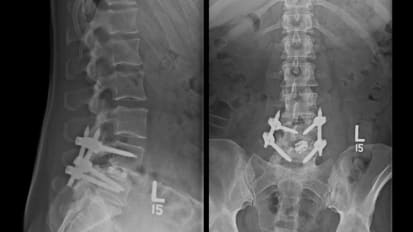

Leading-Edge Approaches and Research to Improve Surgical Spine Treatments and Outcomes

Spine neurosurgeons use technologies co-developed by faculty members to advance patient care. Plus, a first-of-its-kind lab creates a new class of implantable, wearable medical devices to aid those with spinal cord injuries.

Johns Hopkins Medicine Puts Fat to Good Use as Stem Cell Source for Spinal Fusion Surgery

Researchers at Johns Hopkins Medicine suggest there’s another role for the poor maligned adipose cell: a practical and plentiful source of stem cells for use in spinal fusion surgeries.